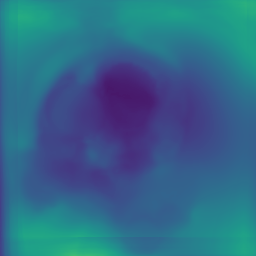

The deformable image registration method is divided into two main stages. For both stages, we used a combination of the CCTA images and segmentation masks. We combined the main cardiac cavities (LV, RV, LA, RA) into a single mask, and combined the aorta (both ascending and descending) and MYO as a second mask (due to the distance between them with low risk of confusion and the advantage of using a small number of masks). In addition, we used two masks corresponding to groups of tissue classified by the density ( and ), after pre-processing the input CCTA images with a median filter with radius 4 to reduce their noise-level and avoid many small objects. The pre-processed intensity images and masks are shown in Fig. 2.